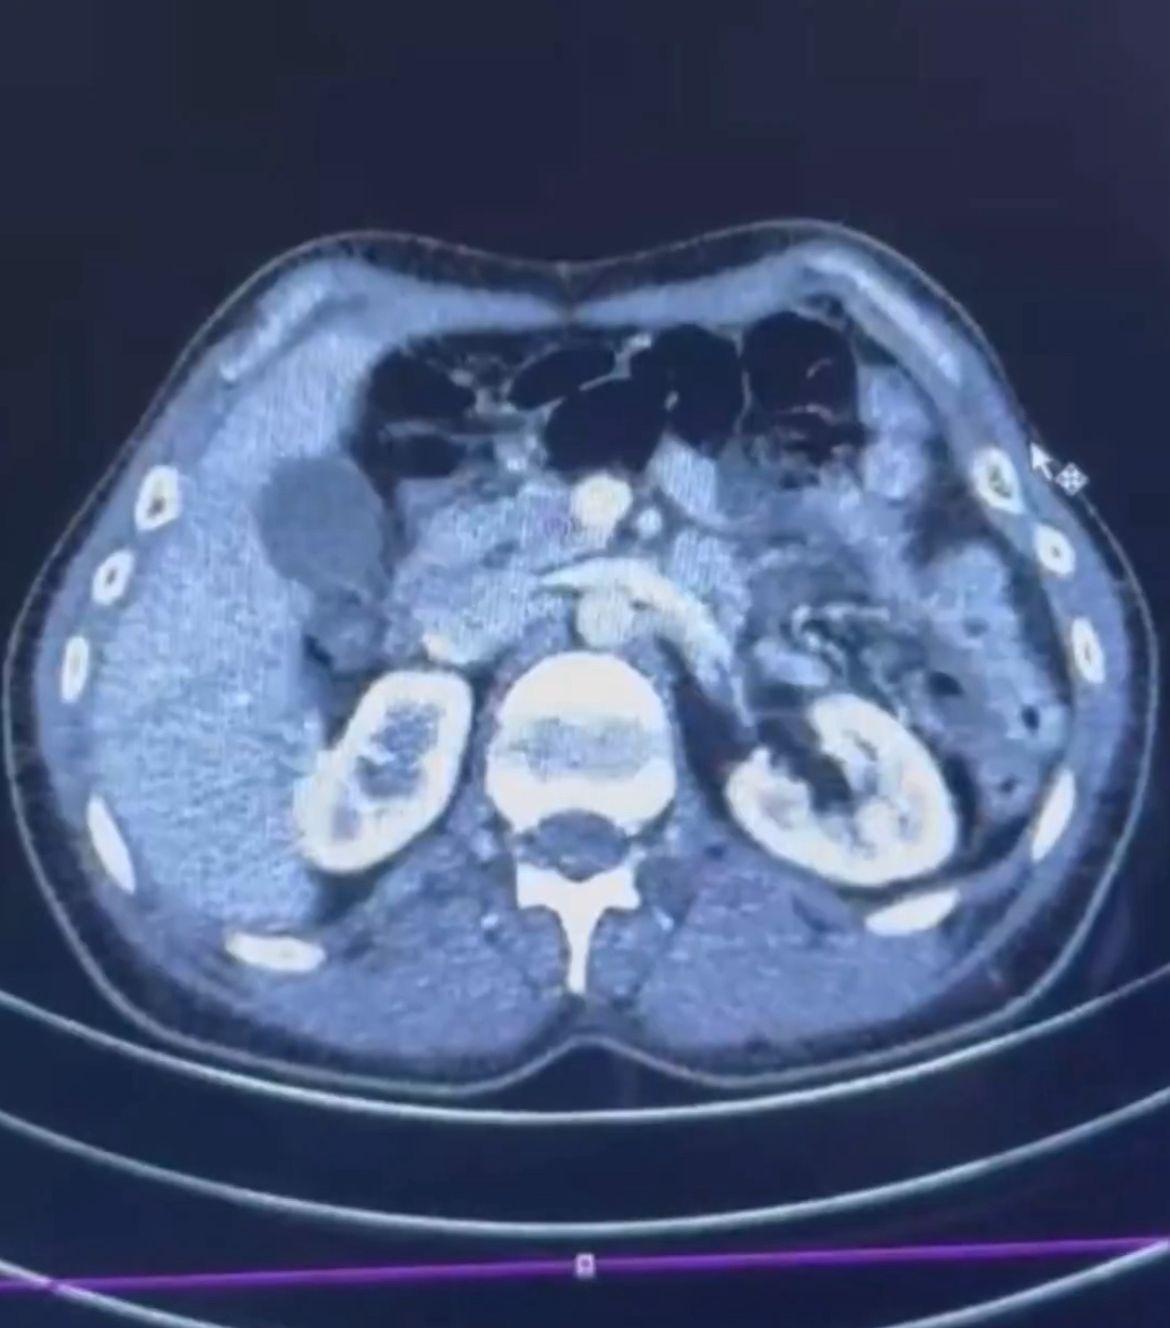

İl Emniyet Müdürlüğü Narkotik Suçlarla Mücadele Şube Müdürlüğü ekipleri, uyuşturucu ticareti yapan kuryelerin yakalanmasına yönelik çalışma başlattı. İran uyruklu 3 şüphelinin yurt dışından Türkiye'ye uyuşturucu getireceği bilgisi alındı. Şüphelilerin bulunduğu adreslere düzenlenen operasyonla S.C. (41), G.M. (28) ve R.B.C. (35) gözaltına alındı. Şüphelilerden S.C. ve R.B.C. muayene edilmek üzere Kayseri Şehir Hastanesi'ne getirildi. Röntgeni ve ultrason çekilen şüphelilerin midesinde yaklaşık 50 kapsülde 554 gram uyuşturucu olduğu tespit edildi. Uyuşturucular sağlık ekiplerinin tedavisiyle çıkarıldı. 3 şüphelinin emniyetteki işlemleri ise sürüyor. (DHA)